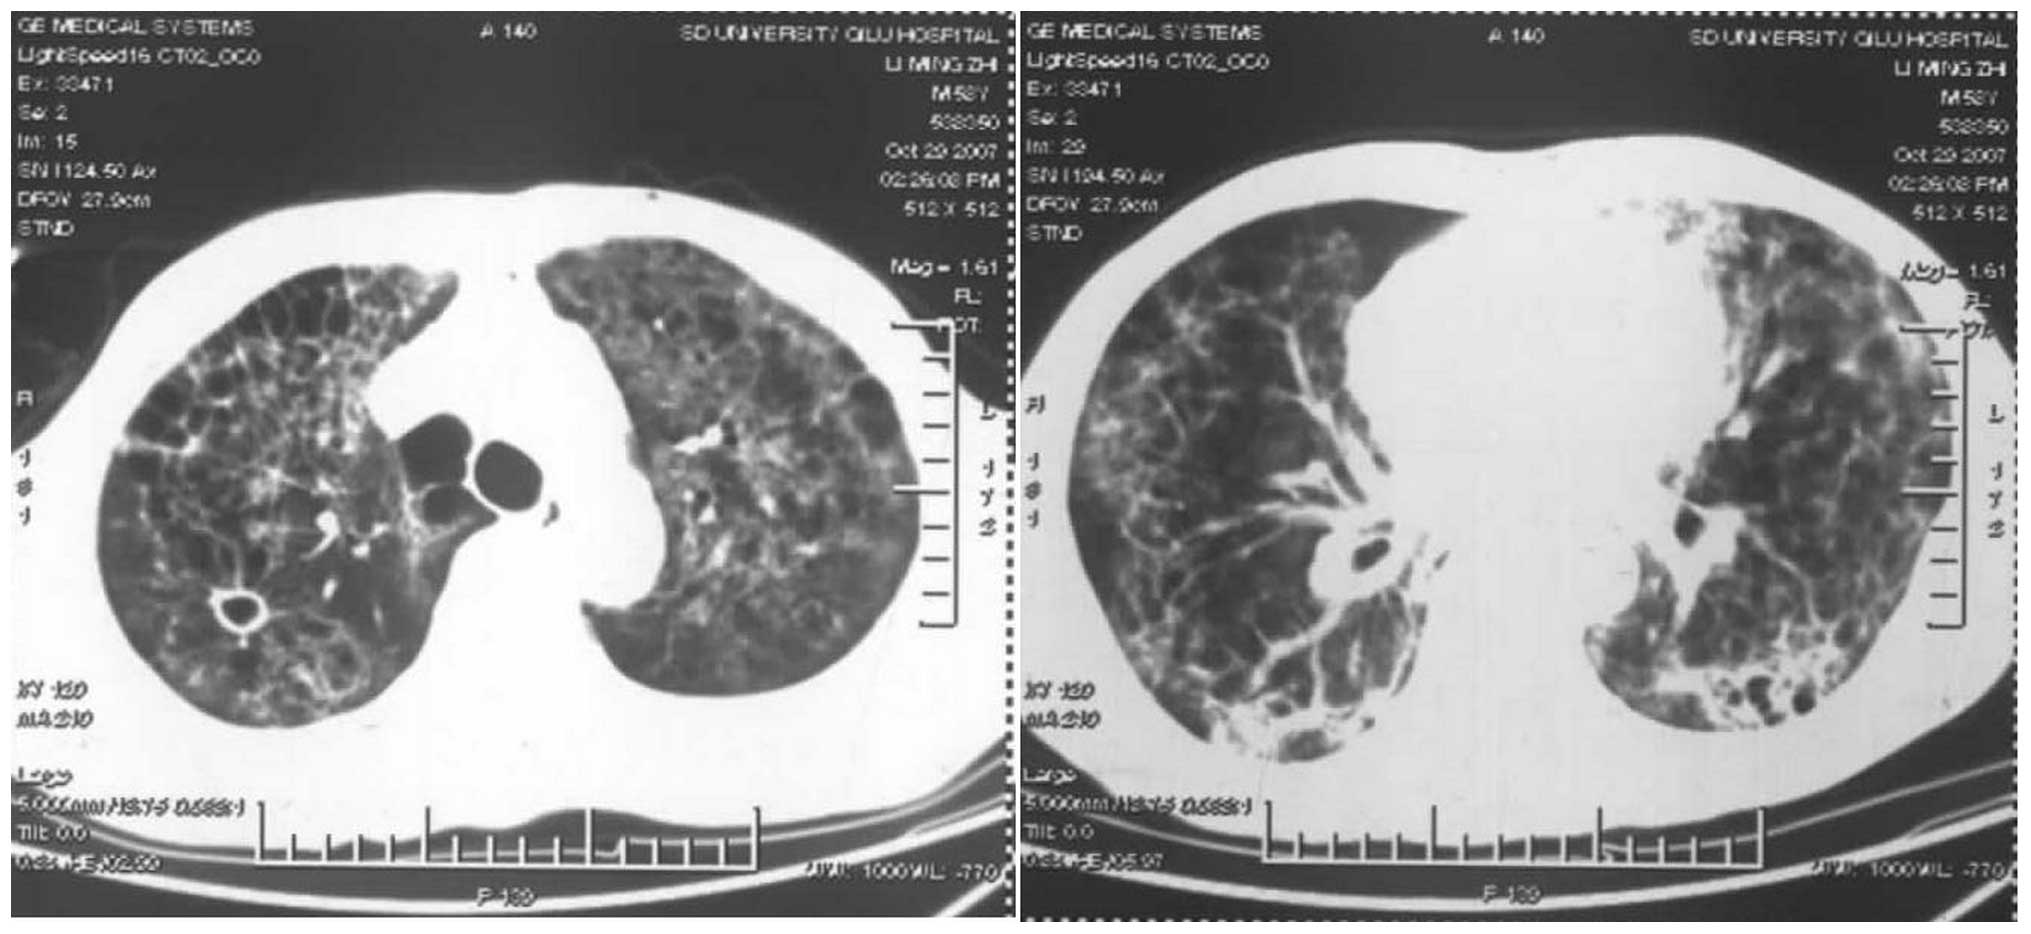

根据文献报道,溃结的肺部并发症包括大、小气道的炎症、肺实质病变、浆膜炎及肺栓塞。这其中,有27%的肺部并发症表现为间质性肺炎,近41%的患者存在气道炎症,而多数的都有不同程度的肺功能下降。

溃结引起的间质性肺炎改变